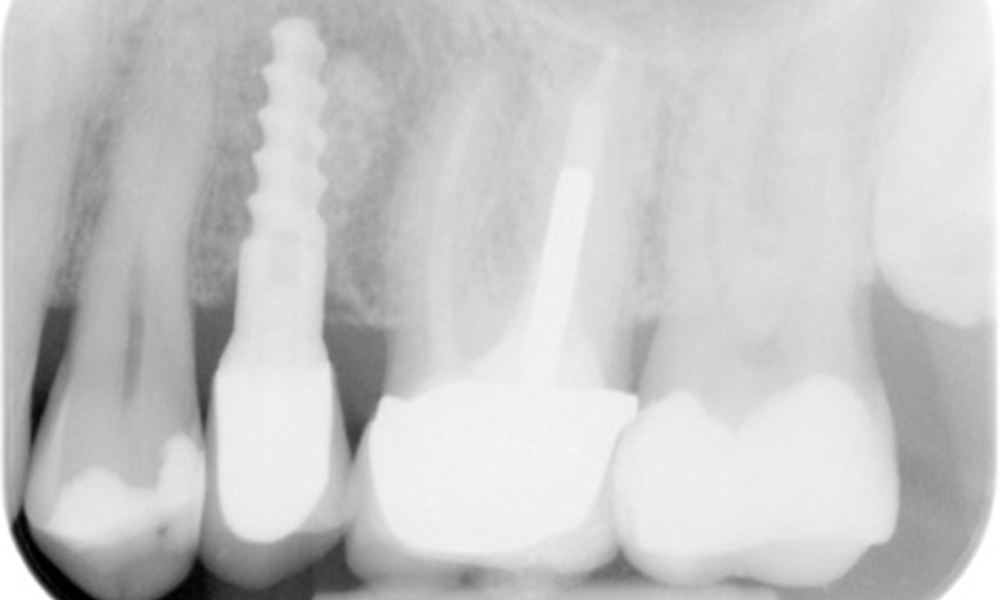

Рентгеновата снимка показва загуба на кост

OPG: 29/02/2024

Рентгенова снимка (или рентгенова снимка на захапката)

Рентгенова снимка (или рентгенова снимка на захапката), заснета на: 18/02/2021